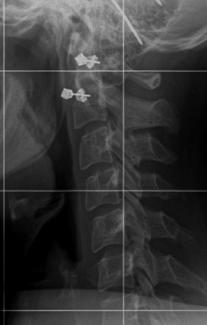

Also, so sieht meine Halswirbelsäule aus (hoffe es klappt mit dem hochladen).

LG

Minimine

HWS mit.jpg

HWS mit.jpg (8 KiB) 6177 mal betrachtet

Es geht einfach darum, bei steilgestellter HWS (HWS Kyphose) und Du hast eindeutig auch eine, in die natürliche HWS Lordose zu kommen.